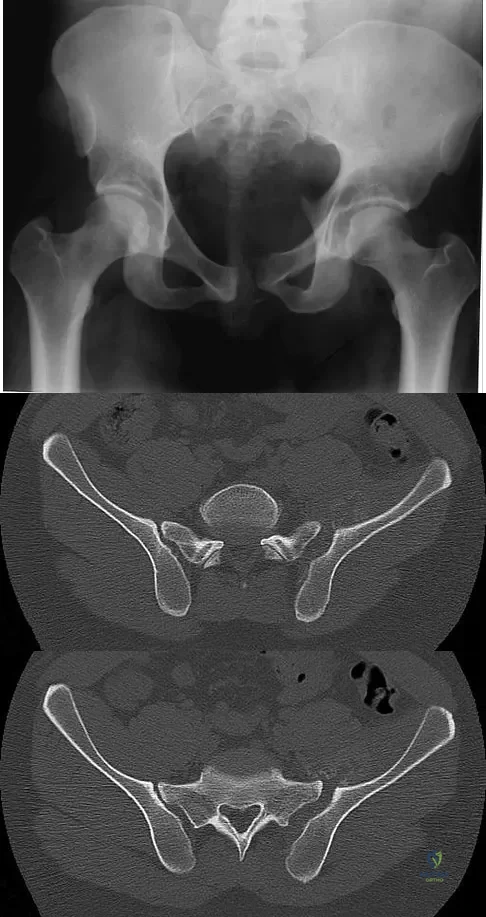

A 20-year-old man is brought to the emergency department after a high-speed motor vehicle accident. His initial blood pressure is 70/40 mm Hg. He is currently receiving intravenous fluids as well as blood. His Focused Assessment with Sonography for Trauma examination did not show any free fluid in his abdomen and his chest radiograph is unremarkable. An AP pelvis radiograph is shown in Figure 15. What is the next most appropriate step in the management of his pelvic injury?

A 30-year-old man who sustained a work-related injury 6 weeks ago reports persistent back and left-sided buttock pain that has been attributed to lumbar transverse process fractures. A pelvic radiograph and CT scans obtained 2 days ago are seen in Figures 17a through 17c. What is the best treatment for his injury?

A 36-year-old woman was injured in a train derailment. She has a significant open depressed skull fracture with active bleeding, a hemopneumothorax, and blood in the left upper quadrant and colic gutter by Focused Assessment with Sonography for Trauma (FAST) examination. Additionally, she has the pelvic injury seen on the CT scans in Figures 18a and 18b. The mortality rate for this patient approaches